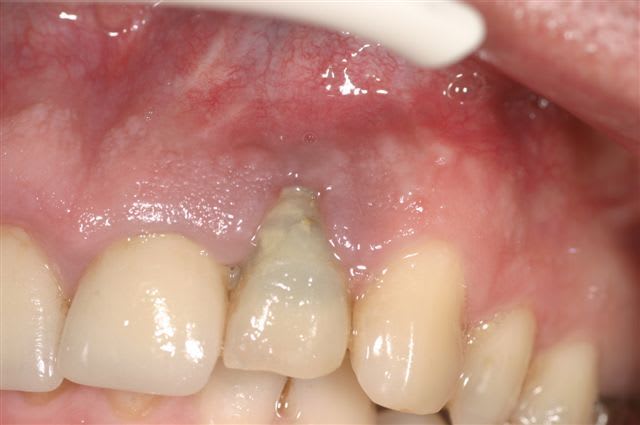

Patiente de 47 ans

La racine de 22 est fracturée verticalement

Extraction de cette dent début avril 2006

Mise en place d’un implant (Seven de MIS) début juillet :

Longueur 13mm x 3,75. Couple de serrage 45N/cm

En raison de la déhiscence osseuse vestibulaire consécutive à la fracture et à l’étroitesse de la crête, l’implant est exposé vestibulairement sur environ 7mm.

Je mets en place du Bio-oss + membrane (Ossix) recouvrant largement le matériau et l’implant. Tout se passe comme dans les livres !

Suites opératoires sans problèmes. Pas d’exposition de la membrane. Tout roule !!

Je revois la patiente aujourd’hui (donc 6 mois après) pour mettre en place le pilier de cicatrisation. J’ouvre….et oh !! stupeur !! les spires sont toujours exposées, recouvertes par une fine épaisseur de tissu de granulation : le bio-oss et la membrane se sont totalement résorbés, mais pas d’os néoformé. Comme si je n’avais rien fait !

Que s’est-il passé ?? Je ne comprends pas !! Si quelqu’un a une explication.